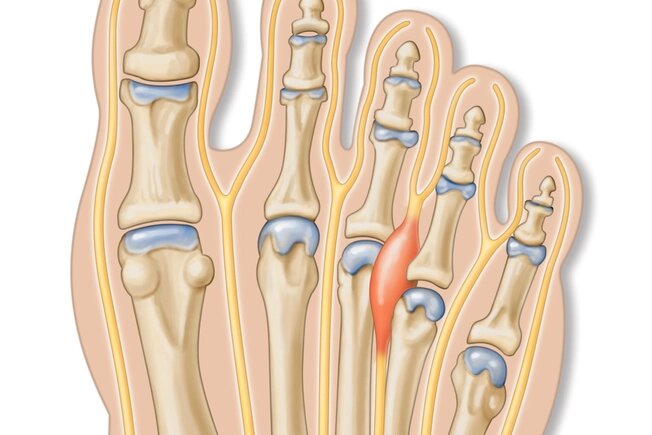

neuromul Morton

Neuronul Morton este o boală a piciorului foarte frecventă. Fiecare a treia persoană o poate avea. Simptomele includ durere în partea din față a piciorului sau senzația ca și cum ați merge pe piatră sau marmură. Acest lucru apare mult mai des la femeile în vârstă și la cele care poartă tocuri înalte sau pantofi strâmți. Schimbarea pantofilor, branțurile și masajul poate ajuta. Dacă durerea devine severă, medicul dumneavoastră vă poate sugera injecții cu steroizi sau intervenții chirurgicale.